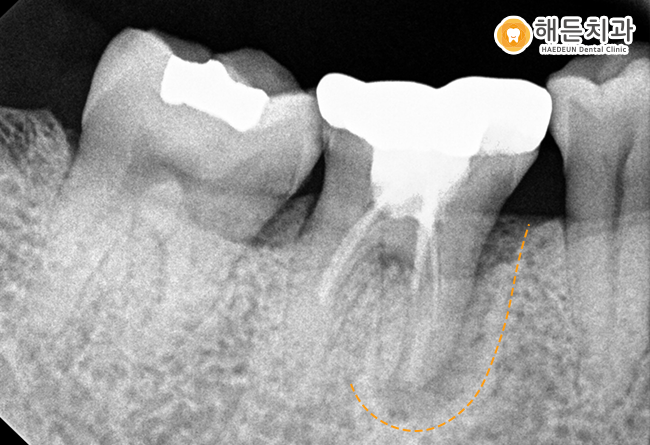

조금 더 정밀하게 체크하기 위해,

해당 치아만 더욱 자세하게 보는

구강 내 작은 사진을 촬영해보았습니다.

앞쪽 뿌리 주변으로 까맣게 비춰보이는 것을 확인하실 수 있는데요.

과거 신경치료를 받았던 치아의 뿌리쪽에

염증이 생겨 뼈가 녹은 모습을 관찰할 수 있었습니다.

위와 같은 상황과 같은 경우 치아를 살리는 방향으로

치료 진행이 어려운 케이스라

환자분과 상담을 진행한 후,

해당 치아는 발치 후 임플란트 치료를 도와드리기로 했습니다.